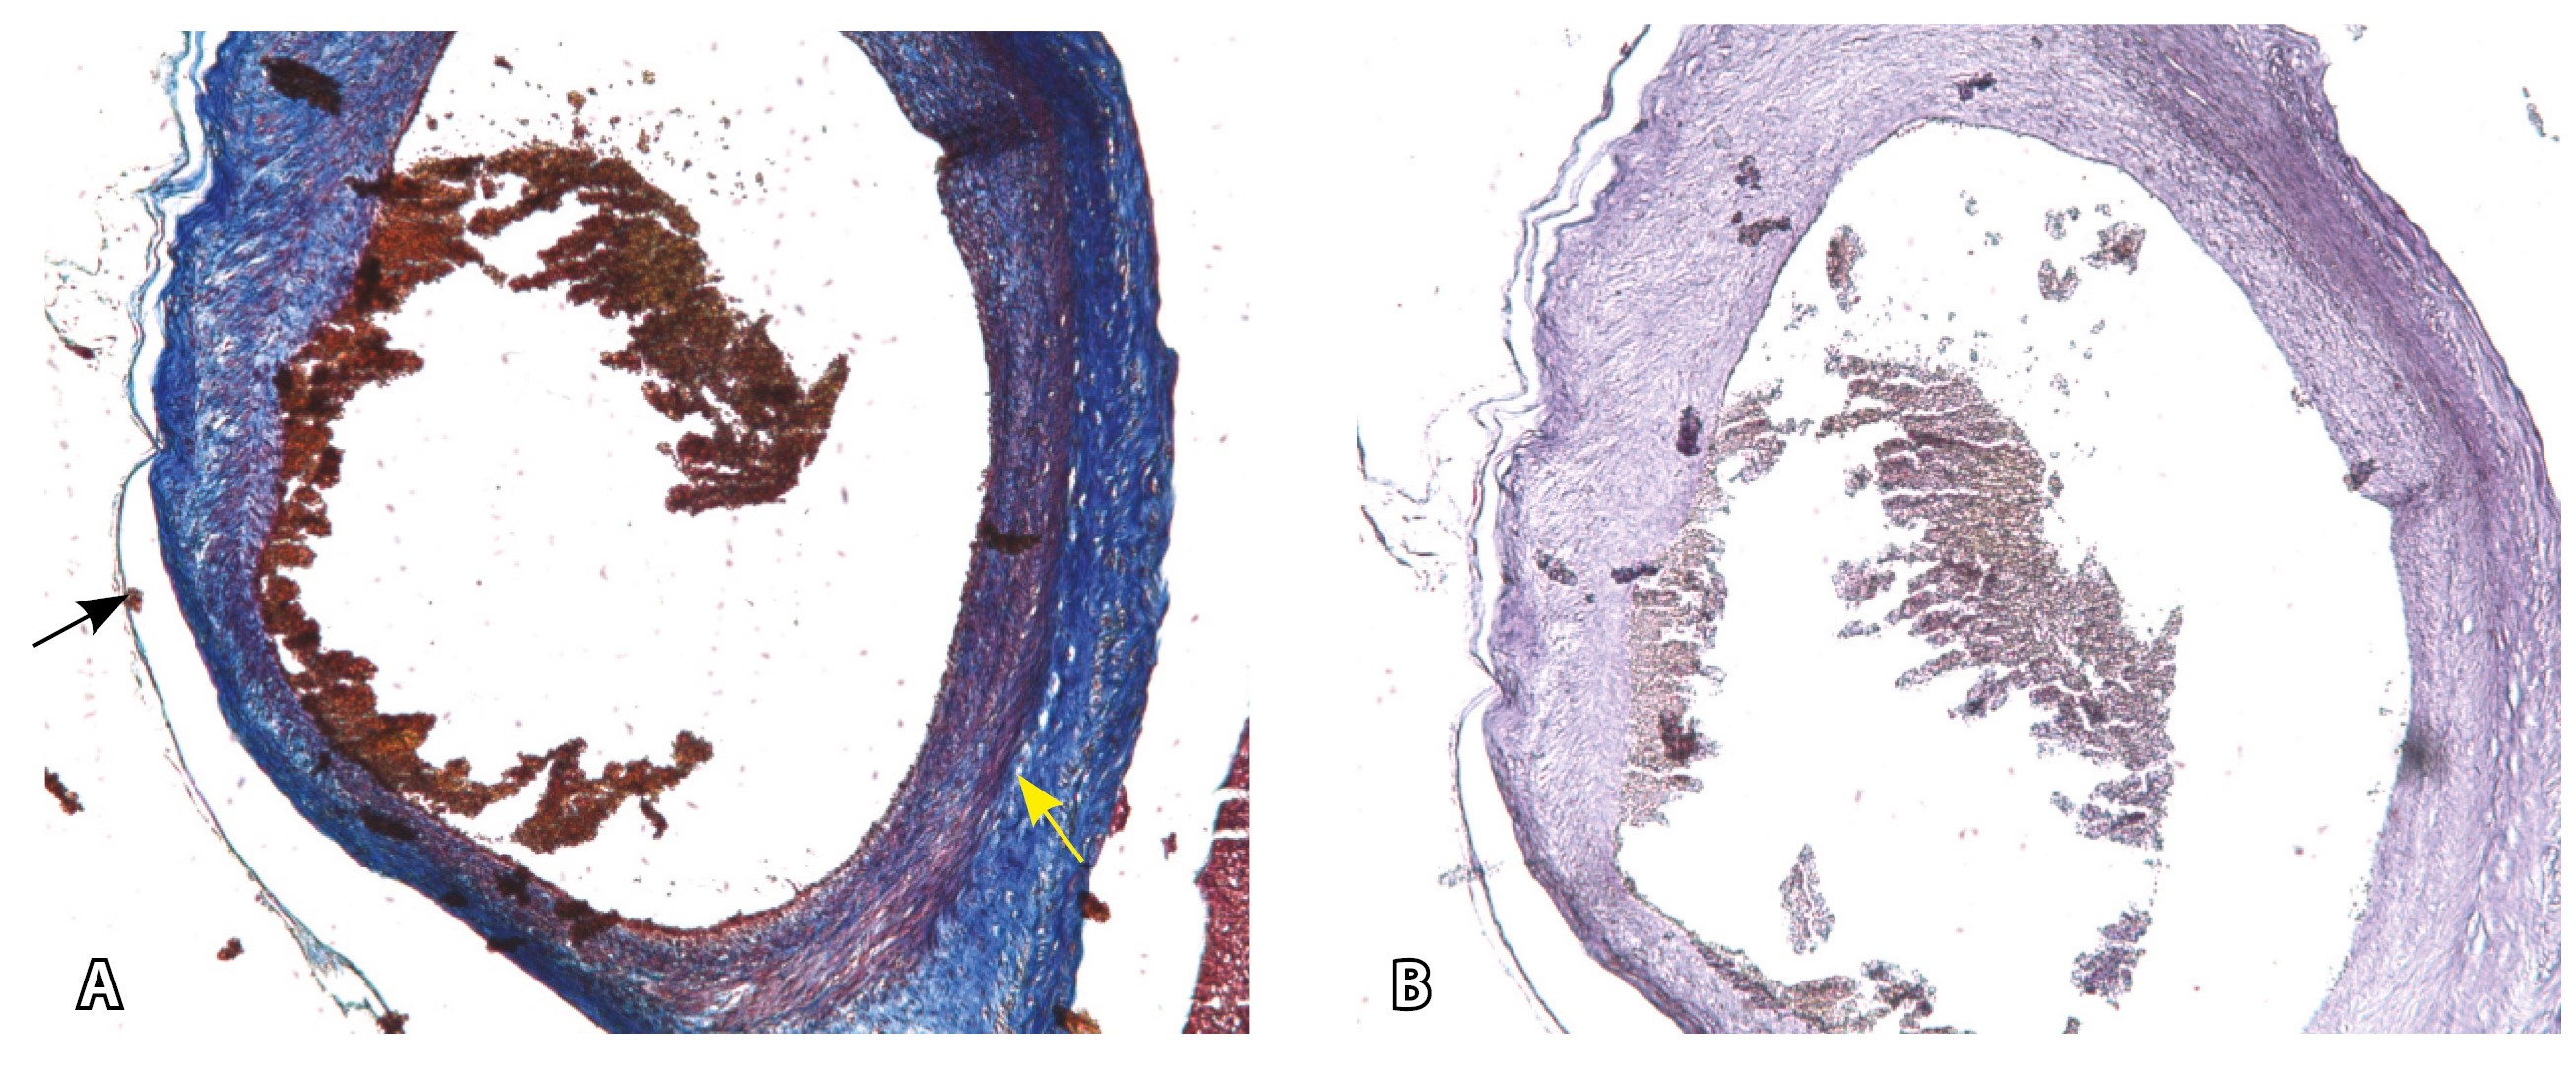

Эластический каркас представлен сетью тонких волокон, без концентрации на внутреннюю и внешнюю мембраны. Однако маркер СD34 констатирует сохранение эндотелия, что свидетельствует о том, что по артериям циркулирует кровь, не сворачиваясь (рис. 13).

Рис. 13. Самые крупные сосуды в пределах серозной оболочки стенки матки: А, Б – серийные срезы артерии; × 50. При окраске по Маллори (А) видна тонкая полоска мезотелия (черная стрелка), слабо дифференцированная мышечная стенка артерии, вокруг нее – плотная коллагеновая оболочка (желтая стрелка), в просвете определяются тромботические массы. При окраске по Вейгерту (Б) наблюдается полная потеря внутренней и внешней эластических мембран

Сосуды 4-го типа встречались как при pl. increta (16,7%) (PAS 2 по FIGO), так и при pl. percreta (100%) в пределах серозного слоя матки (PАS 3a по FIGO). Обнаружено наличие крупных извитых анастомозирующих сосудов, преимущественно по поверхности матки, в сочетании с выраженным истончением рубца от КС. Главное отличие сосудов этого типа – локализация в пределах серозного слоя матки, с наличием тонкого поверхностного слоя мезотелия на микропрепаратах по их поверхности. Этот феномен можно объяснить тем, что в случае прикрепления трофобласта и затем плаценты к рубцу от КС при прогрессировании беременности плацента оказывает паракринное влияние в том числе посредством факторов ангиогенеза, в результате чего нельзя исключить рост сосудов из бассейнов маточных артерий с целью обеспечения трофической функции матки и сохранения беременности. Указанный патогенетический механизм также подтверждают описанные в литературе случаи брюшинной беременности [17]. Кроме того, нельзя исключить, что локальная ишемия стенки матки в области врастания может способствовать увеличению ангиогенеза и васкулогенеза. При выполнении МРТ невозможно достоверно визуализировать серозный слой матки из-за его малой толщины, поэтому создается впечатление о локализации сосудов за пределами стенки матки. По данным патоморфологического исследования, для этого типа характерно наличие крупных сосудов, анастомозирующих друг с другом. В стенках артерий трудно различимы 2 слоя миоцитов, по наружной поверхности сосуды окружены толстым «футляром» из грубоволокнистой соединительной ткани, которая проникает в стенку артерий и замещает мышечный слой. Эластический каркас представлен сетью тонких волокон, без концентрации на внутреннюю и внешнюю мембраны. Генез возникновения таких сосудов до конца не изучен. В ряде исследований, посвященных беременности, расположенной в проекции рубца от КС, отмечается наличие артериовенозных соустий по типу мальформации в данной области даже на ранних сроках беременности, которые, возможно, продолжают функционировать и на более поздних сроках и становятся еще более полнокровными [18–20].